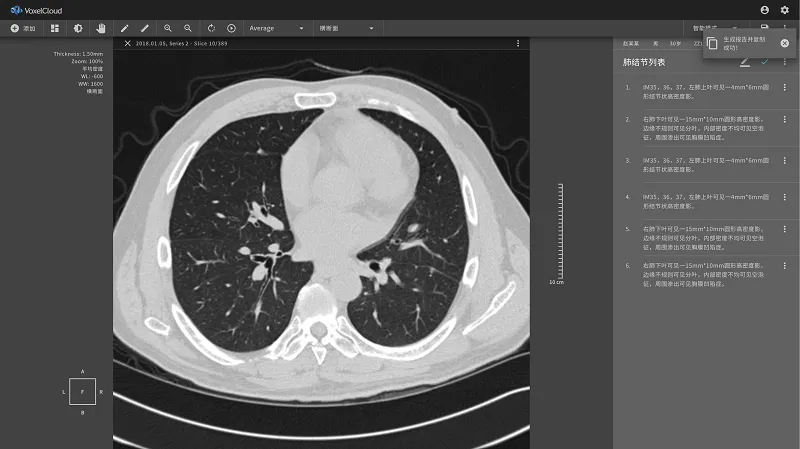

眼下,基于大量的深度访谈和统计数据,体素科技为医院和体检中心提供针对影像类型的智能阅片解决方案,自动诊断和撰写影像视野可见范围内的所有异常,譬如胸部CT、心脏冠脉造影CT等。

肺癌筛查产品

从过去两年的情况来看,在国内的智能医疗环境中,用丁晓伟的话说,诸如肺癌CT筛查的解决方案等直接解决效率问题的应用普及门槛相对较低,也没有用户学习和培养的过程,因此在国内的普及度较高。